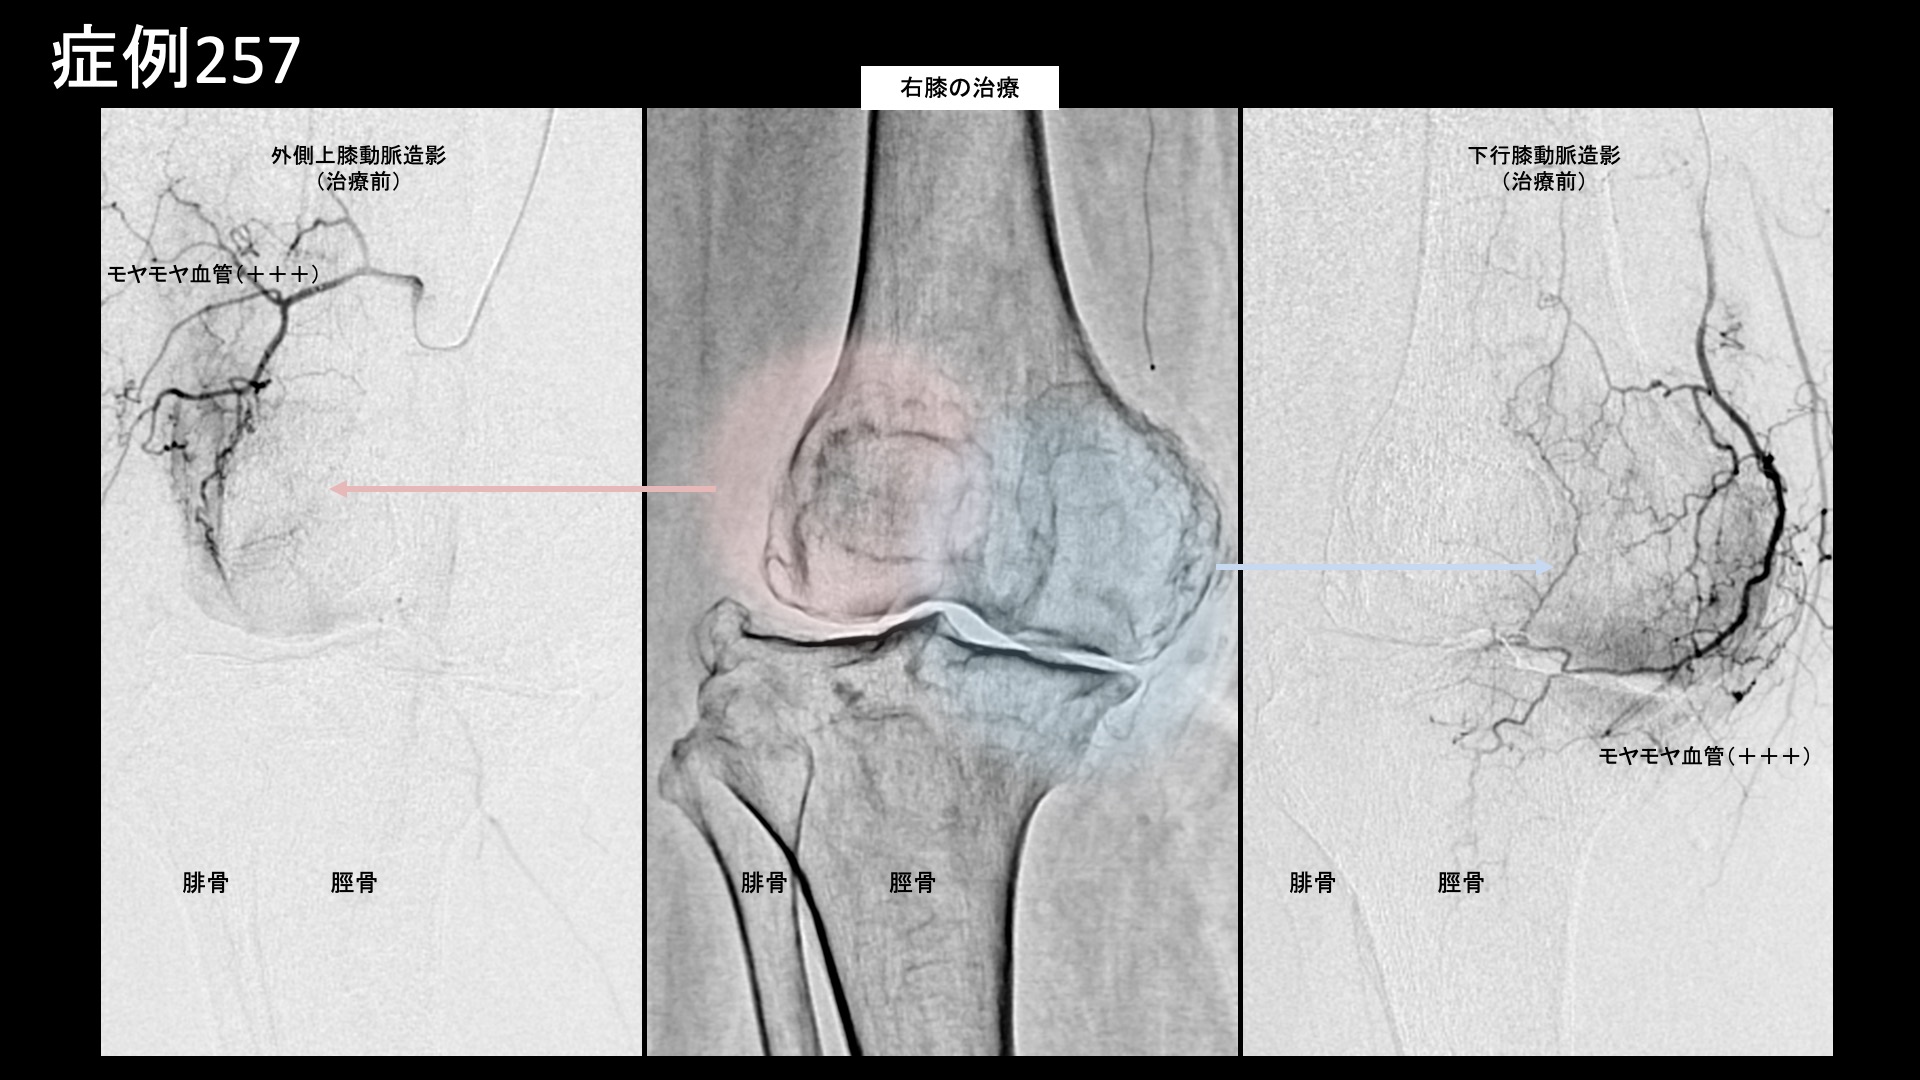

まず膝の治療から始めました。血管造影を行うと、全ての血管でモヤモヤ血管(病的新生血管)が造影剤の濃染像として描出されました。写真では、外側上膝動脈、下行膝動脈の造影所見を示しています。典型的な変形性膝関節症の所見です。治療後、モヤモヤ血管は画像上速やかに消失しました。続いて両足首および左踵の治療です。足関節は膝と比べると、ある程度重症度が増してこなければモヤモヤ血管が明確には描出されにくい部位ですが、本症例では主要3血管(前脛骨動脈、後脛骨動脈および腓骨動脈)の全てにおいてモヤモヤ血管が認められました。左足では、さらに踵骨棘近傍にも明瞭に描出されました。滞りなく治療を行い終了しました。